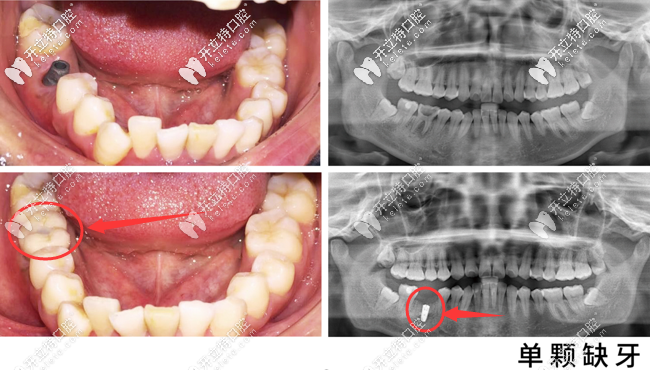

美奧口腔單顆種植牙真人案例▼

蘇州美奧口腔單顆種植牙案例